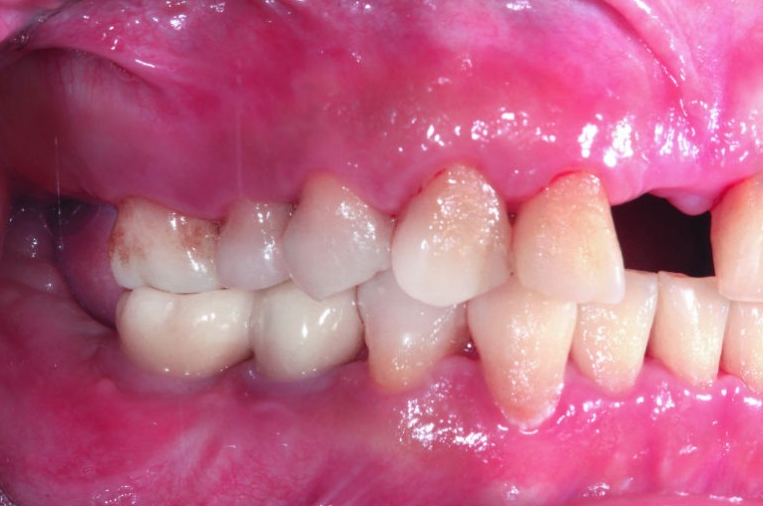

缺牙區以植牙重建功能,只要血糖穩定牙周健康,可以達到與一般人接近的植牙成功率(圖片來源/新光醫院提供)